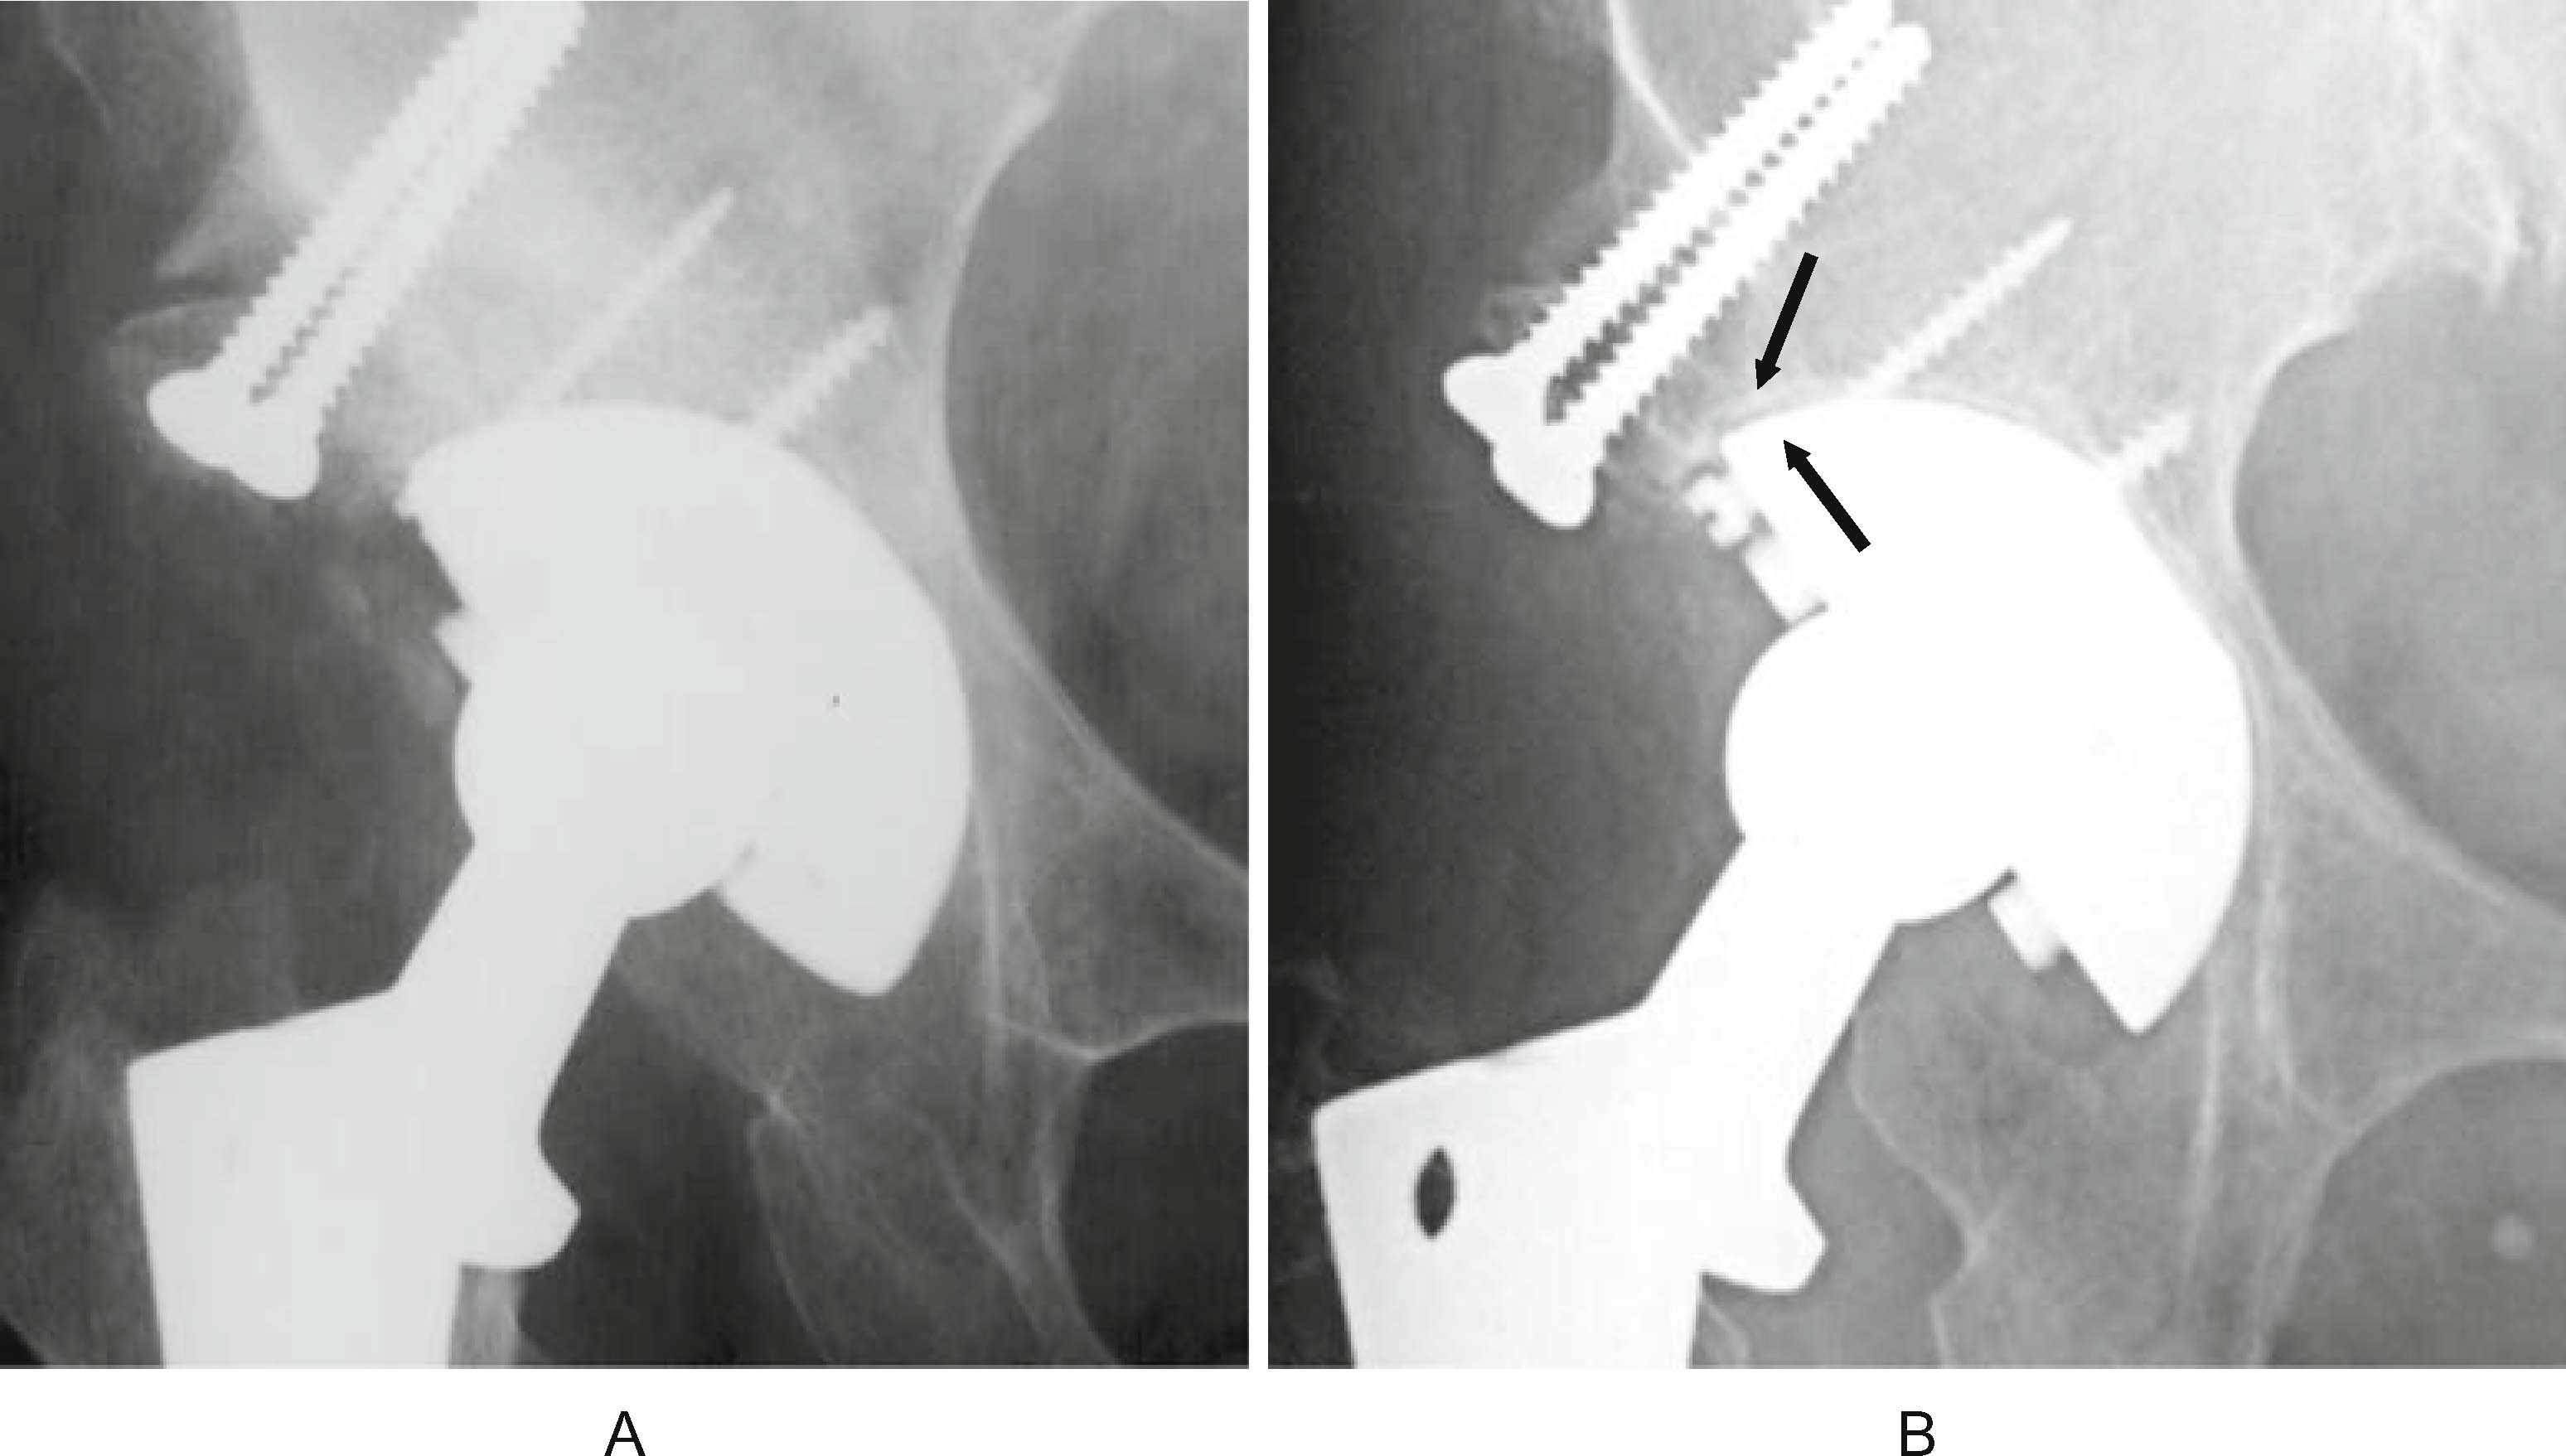

From link.springer.com

Cementless total hip replacement past, present, and future SpringerLink Cementless Hip Replacement Recovery Time Quality of life (after primary total hip replacement, revised total. The aim of the study was to investigate functional outcome and quality of life 4 weeks and 12 months after cementless total. “on average, hip replacement recovery can take around two to four weeks, but everyone is different,” says thakkar. The aaos reports that most people will be able to. Cementless Hip Replacement Recovery Time.

From www.semanticscholar.org

[PDF] Current Concepts Review Cementless Femoral Fixation in Total Hip Cementless Hip Replacement Recovery Time It depends on a few factors, including how active you were. The aaos reports that most people will be able to resume most light activities of daily living independently within 3 to 6 weeks. Quality of life (after primary total hip replacement, revised total. Assuming that estimates from national registries are less likely to be biased, patients and surgeons can. Cementless Hip Replacement Recovery Time.

Cementless Long Stem Total Hip Replacement for Revision of Failed Cementless Hip Replacement Recovery Time For the cost effectiveness analysis model we estimated several parameters from individual patient data: Assuming that estimates from national registries are less likely to be biased, patients and surgeons can expect a hip replacement to last 25 years in around 58% of patients. It depends on a few factors, including how active you were. Quality of life (after primary total. Cementless Hip Replacement Recovery Time.